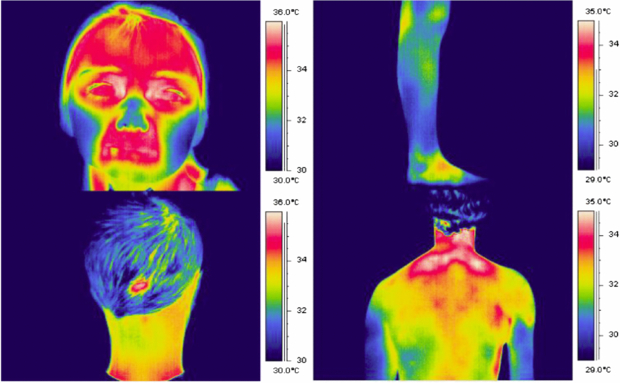

Changes in tissue perfusion often result in a change in tissue temperature. This is the principle of thermography for microvascular imaging: it uses an infrared thermal imaging camera to determine tissue temperature from the human body. Figure 9 shows examples of false-colour thermograms recorded from various skin sites using a modern 320 × 240 pixel thermal imager.

Figure 9. Example thermograms of the temperature distribution of the human body, recorded using the FLIR SC500 thermal imager (320 × 240 pixels, 7–14 µm waveband).

Download figure:

Standard image High-resolution image2.3.1. Background